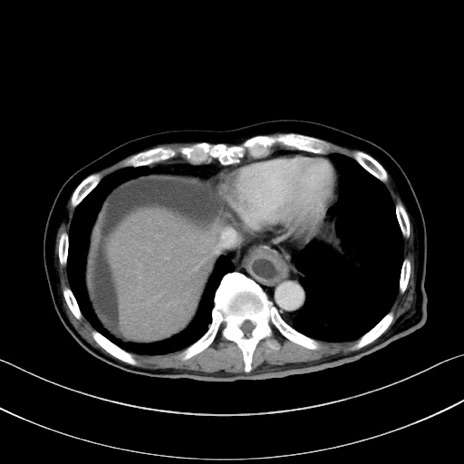

症例28(横断像)

【症例】60歳代男性

【主訴】嘔吐

【現病歴】胃癌にて胃全摘後。食思不振が悪化し、夜中に嘔吐することがある。

【既往歴】胃癌、胃全摘、脾摘、胆摘後

【データ】WBC 5900、CRP 10.56